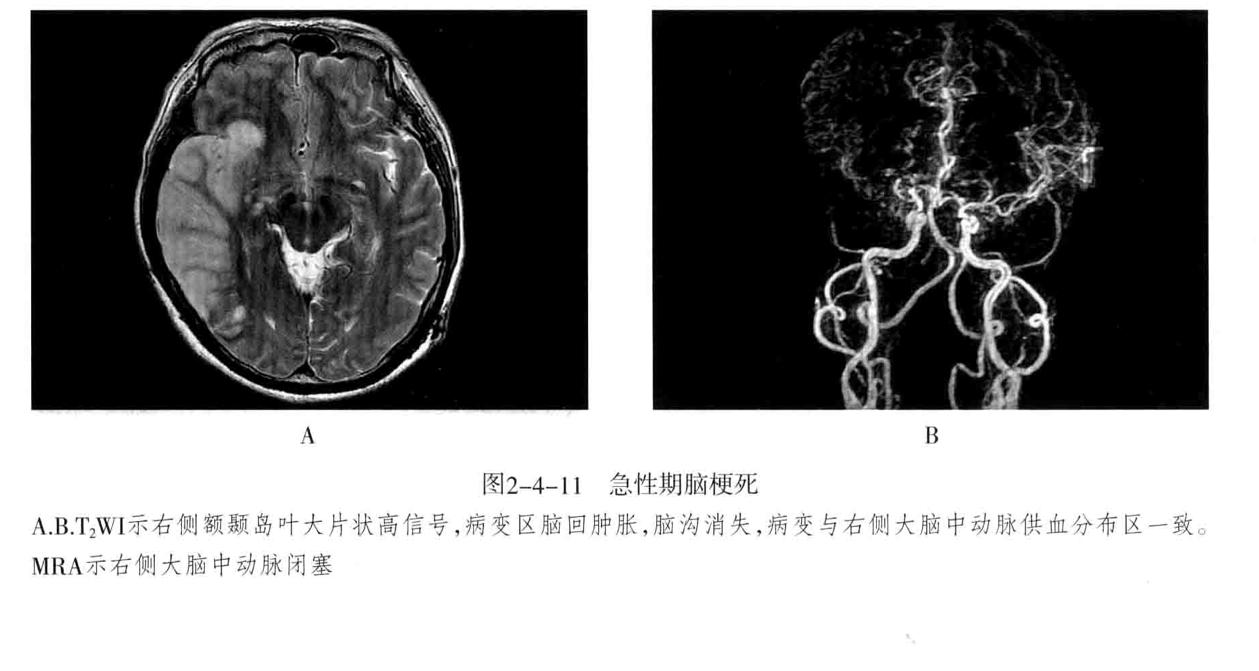

八、脑梗死:是一种缺血性脑血管疾病,常见有动脉闭塞性梗死和腔隙性脑梗死。主要病因为脑的大或中等管径的动脉发生粥样硬化,继发血栓形成,导致管腔狭窄、闭塞。以大脑中动脉闭塞最常见。脑梗死发生4-6小时脑组织发生缺血与水肿,继而脑组织出现坏死。1-2周后脑组织水肿逐渐减轻,坏死脑组织液化,梗死区出现吞噬细胞浸润,清除坏死组织,同时有胶质细胞增生和肉芽组织形成,8-10周后形成含液体的囊腔即软化灶。少数缺血性脑梗死在发病24-48小时后可因再灌注而发生梗死区内出血,转为出血性脑梗死。常见症状为偏瘫和偏侧感觉障碍、偏盲、失语等。

1. CT表现为脑组织内低密度灶,梗死后2-15天为脑水肿高峰期,此时可有脑水肿表现;梗死1个月以后,相邻部位的脑室、脑池或脑沟扩大,出现脑萎缩表现。增强后梗死区可出现不均匀强化,呈脑回状、条状、环状或结节状强化。梗死区强化是由于血脑屏障破坏、新生毛细血管和血液灌注过度所致。

2. MRI在脑梗死6小时之内,由于细胞毒性水肿,DWI可发现高信号,此后发生血管源性水肿、细胞死亡、髓鞘脱失、血脑屏障破坏,T1与T2弛豫时间延长。梗死后期,小的病灶不显示,表现为脑萎缩,大的病灶表现为软化灶。